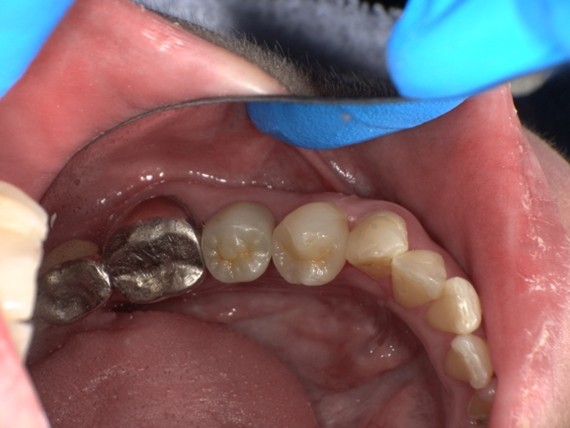

【症例No.2】左上奥歯インレー修復/40代女性

Before

After

古い詰め物を除去を行いセラミック(emax)にて修復を行いました。噛む力が強い方の場合は少し透明感は落ちてしまいますがジルコニアという素材を使うことにより強度を担保できます。